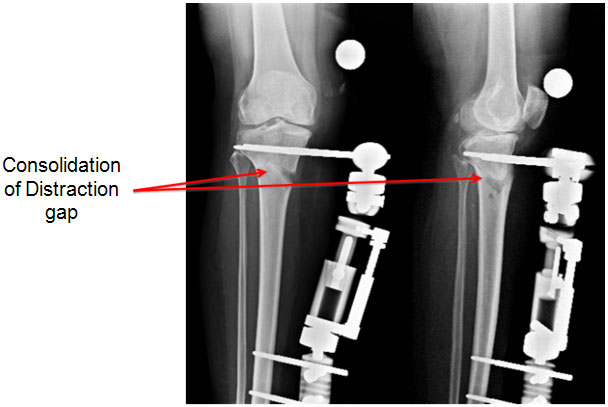

| 7 weeks |

| |